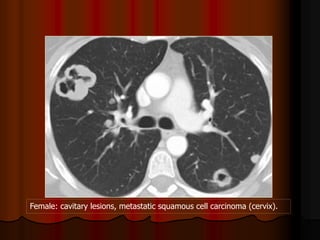

Female: cavitary lesions, metastatic squamous cell carcinoma (cervix).

Mỗi hang thường có một banh nấm